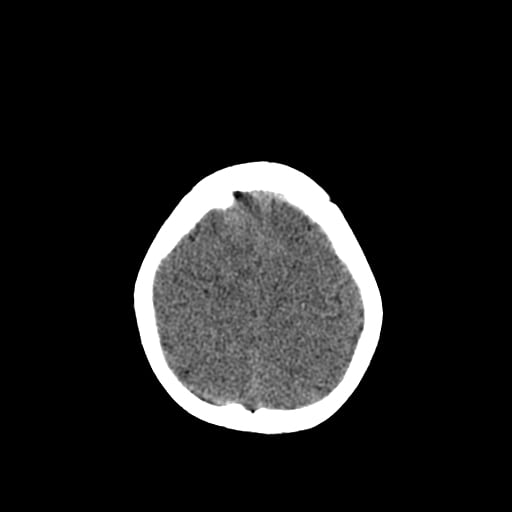

Age: 1

Sex: Male

Indication: Fall